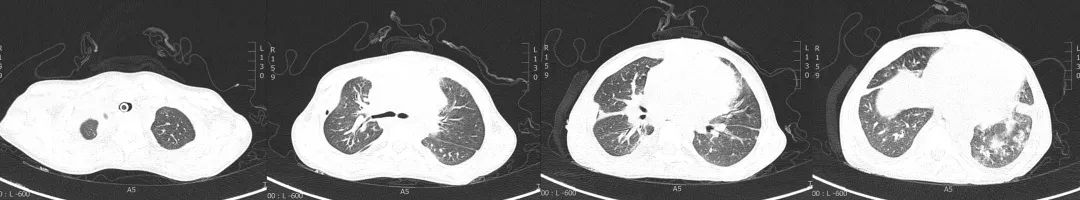

经过临床-康复-护理积极地综合治疗与管理,影像学对比发现:各叶段支气管通畅,双侧胸腔积液及心包腔积液较前减少。

图:2019年6月10日CT

图:2019年7月24日CT